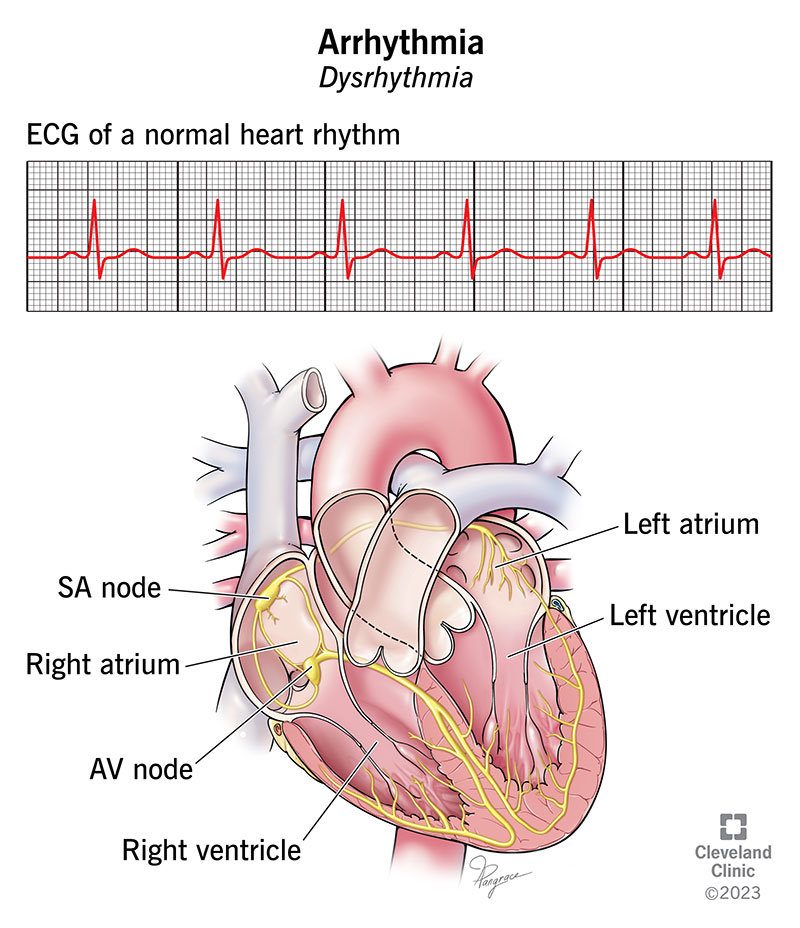

Heart Arrhythmias - Physiopedia

www.physio-pedia.comHeart Arrhythmias - Physiopedia

www.physio-pedia.comHeart Arrhythmias - Physiopedia

Arrhythmia: Types, Causes, Symptoms, And Treatment

www.medicalnewstoday.comArrhythmia: Types, causes, symptoms, and treatment

www.medicalnewstoday.comArrhythmia: Types, causes, symptoms, and treatment